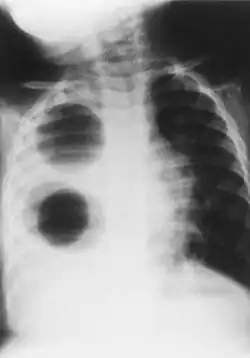

• Chest X-ray is effective in detecting the traits of lung herniation.[1] The unaffected side of lung tends to undergo hypertrophy, and move towards the empty space in the chest wall on the opposite side.[1] This herniation could be indicated by fluoroscopy.[1] With age increasing, the herniation progresses and ease its detection.[1]

Chest radiograph of a 3-year-old who underwent right pulmonary plombage with insertion of three Ping-Pong balls 1 year earlier.[13]